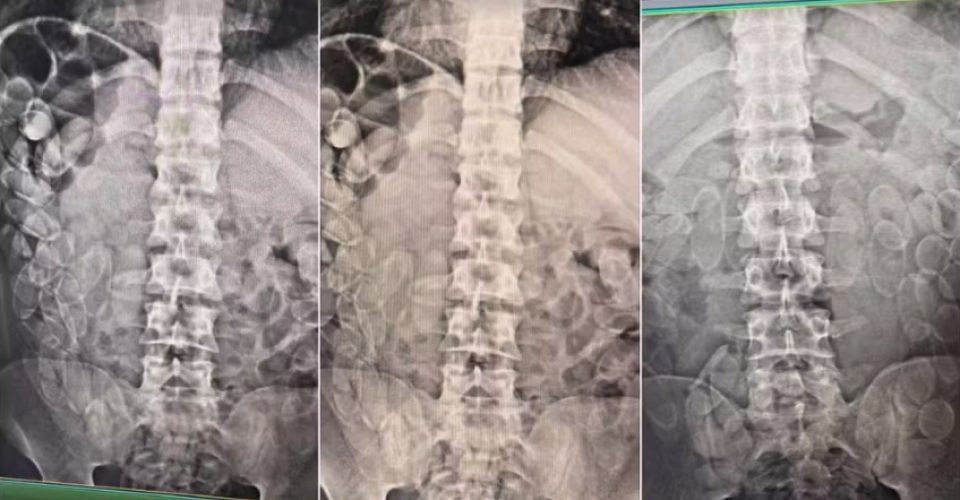

Nesta segunda-feira (17), três bolivianos de 21, 27 e 31 anos, foram detidos após ingerirem cerca de 300 cápsulas de cocaína. As autoridades encontraram aproximadamente 5 kg de pasta base de cocaína, parte dela camuflada em um frasco de condicionador de cabelo e na cueca de um dos suspeitos. O restante da droga foi engolido pelos indivíduos. O caso aconteceu durante fiscalização na BR-262, em Corumbá, cidade distante 425km de Campo Grande.

Os suspeitos informaram à polícia que cada um ingeriu cerca de 100 cápsulas e que o destino da droga era São Paulo, onde seriam pagos pelo transporte. Além da cocaína, também foram encontradas cerca de 2 toneladas de roupas falsificadas e alimentos contrabandeados nos veículos.

Segundo informações do G1, os bolivianos foram encaminhados à Santa Casa de Corumbá, onde expelirão as cápsulas, e depois serão levados à Delegacia da Polícia Federal para as devidas providências.